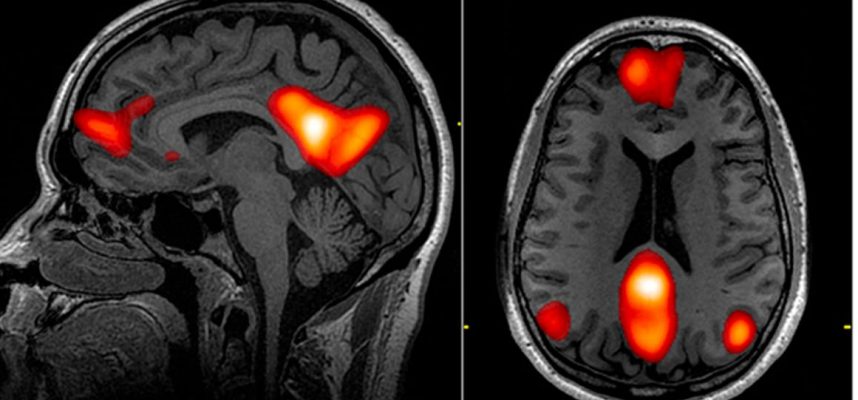

За да обобщим някои от бързо натрупващите се данни, двама невролози прегледаха проучвания, изследващи как COVID-19 нарушава модели на нормална мозъчна функция, които могат да бъдат измерени с ЕЕГ.

ЕЕГ, съкратено от електроенцефалограма, записва електрическата активност в различни части на мозъка на човек, обикновено използвайки електроди, поставени върху скалпа.

ЕЕГ сканирането на пациентите показва спектър от аномалии в мозъчната дейност, включително някои ритмични модели и епилептични изблици на активност. Най-честата забелязана аномалия е дифузно забавяне, т.е. общо забавяне на мозъчните вълни, което е показателно за обща дисфункция на мозъчната дейност.

По отношение на локализираните ефекти, една трета от всички открити аномалии са открити във фронталния лоб, частта от мозъка, която изпълнява задачи на изпълнително мислене като разсъждения и вземане на решения. Фронталният лоб също ни помага да регулираме емоциите си, да контролираме поведението си и участва в ученето и вниманието.

„Тези данни ни казват, че трябва да опитаме ЕЕГ при по-широк кръг пациенти, както и други видове изображения на мозъка, като ЯМР или КТ, които ще ни позволят да разгледаме по-отблизо фронталния лоб“, каза неврологът и съавтор на изследването Зулфи Ханиф. от Медицинския колеж Baylor в Хюстън.